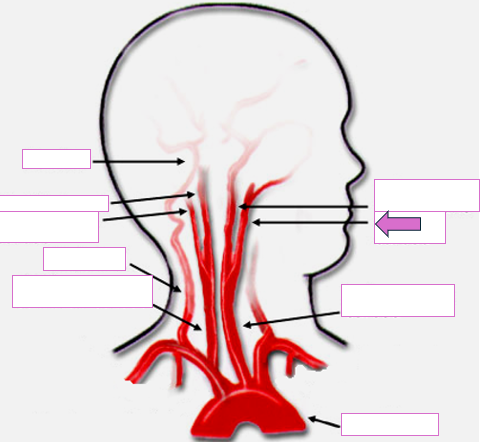

Based on the indicated area, identify this vessel

Brachiocephalic/innominate artery

Right subclavian artery

Right vertebral artery

Right carotid artery

Left carotid artery

Left vertebral artery

Left subclavian artery

Basilar

Right internal carotid

Right external carotid

Vertebral

Right common carotid

Left internal carotid

Left external carotid

Left common carotid

Aortic arch